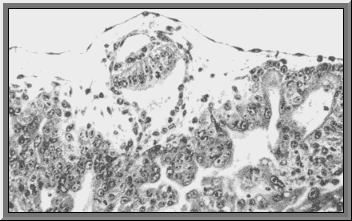

The embryoblast develops into the epiblast. The epiblast, sandwiched between trophoblast and hypoblast forms the embryo.

Between the epiblast and the trophoblast a cavity is formed, the amniotic cavity.